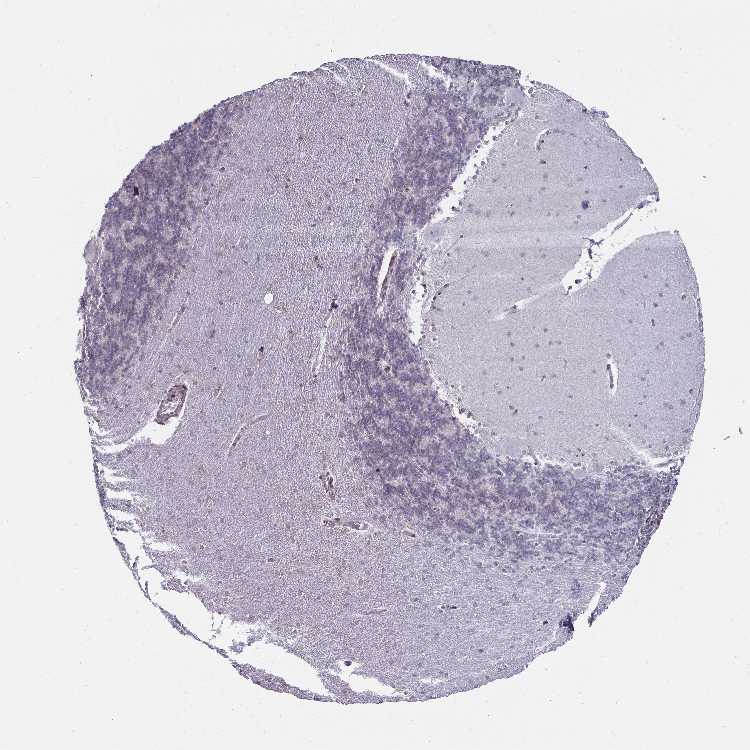

CEREBELLUM - Antibody stainingi

Antibody staining in the annotated cell types in the current human tissue is reported as not detected, low, medium, or high, based on conventional immunohistochemistry profiling in selected tissues. This score is based on the combination of the staining intensity and fraction of stained cells.

Each image is clickable and will lead to virtual microscopy that enables deeper exploration of all samples and also displays staining intensity scores, fraction scores and subcellular localization as well as patient and tissue information for each sample.

Antibody HPA000609Antibody CAB001545Antibody CAB002029Antibody CAB062552

Purkinje cells Not detectedNot detectedNot detectedNot detected

Cells in granular layer Not detectedNot detectedNot detectedNot detected

Cells in molecular layer Not detectedNot detectedLowNot detected